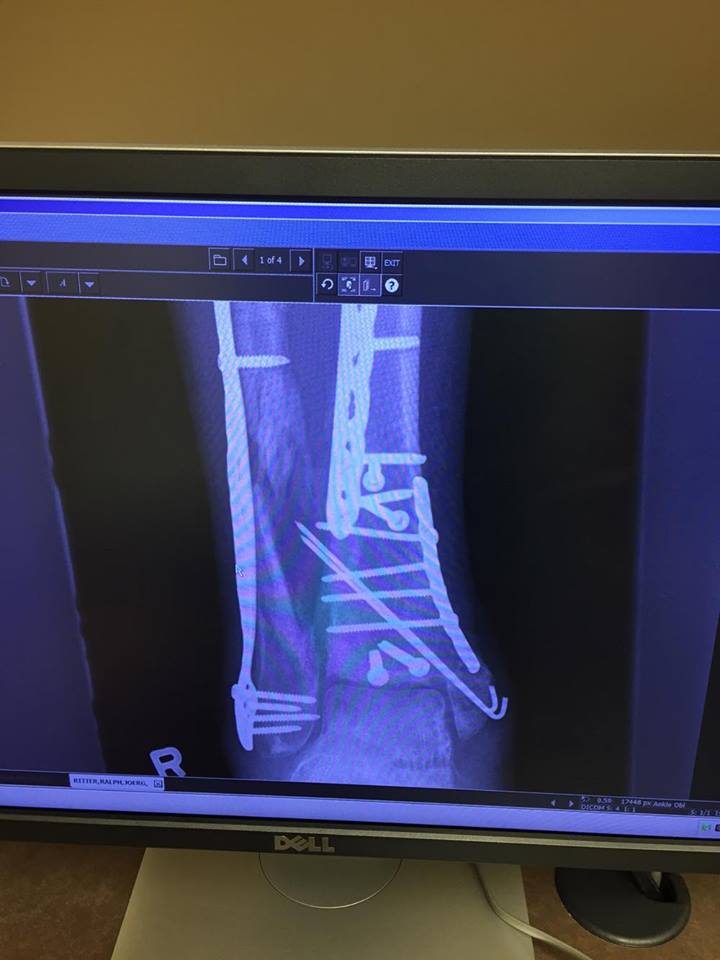

- Shattered right ankle, compound fracture to right tibia and fibula, right knee just below the joint fractured,

- A bone infection caused painful problems during his 5.5 week recovery in the hospital and muscle atrophy issues around the spine are ongoing with surgeries planned to try and correct it

A large part of the credit goes to his protective gear too. He was decked out in MOST of his good quality equipment that day, but for whatever reason neglected to wear his riding boots. He’s convinced the damage sustained to his right leg would have been lessened had he been a little wiser in his choice of footwear.